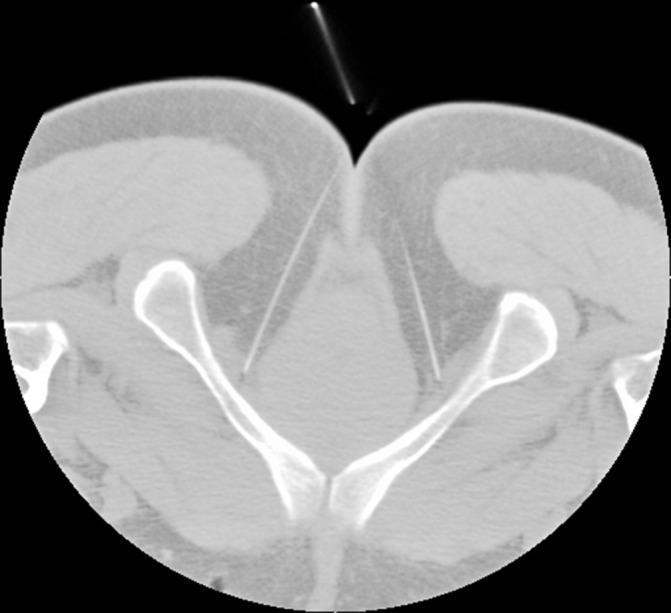

Electroacupuncture at 'four sacral points', also known as electrical pudendal nerve stimulation therapy, combines the advantages of pudendal nerve neuromodulation and the technique of deep insertion of long acupuncture needles. It has been used to treat stress urinary incontinence, female urgency-frequency syndrome, idiopathic urgency urinary incontinence and neurological bladders in previous studies. Here, we describe the protocol for a randomised controlled trial for evaluation of the efficacy and safety of electroacupuncture at 'four sacral points' for the management of urinary incontinence after stroke.

电针“骶四穴”,又称阴部神经电刺激疗法,结合了阴部神经神经调节和深刺长针技术的优点。既往研究中,该方法已被用于治疗压力性尿失禁、女性尿急-频综合征、特发性急迫性尿失禁和神经源性膀胱。在此,我们描述了一项评估电针“骶四穴”治疗中风后尿失禁疗效和安全性的随机对照试验方案。